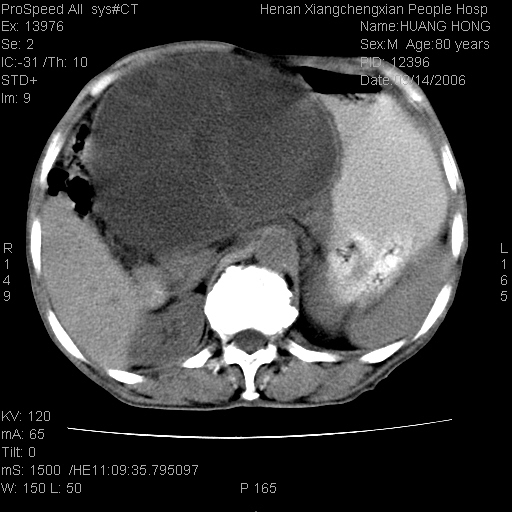

患者, 男, 80岁, 发现上腹部包块1年余,无其它不适.2006-9-14ct片是喝水后扫描2006-9-15ct片没喝水扫描![]() ![]() ![]() ![]() ![]() ![]() ![]() ![]() ![]() ![]() ![]() ![]() ![]() ![]() ![]() ![]() 以上是喝水片 以下是空腹片 ![]() ![]() ![]() ![]() ![]() ![]() ![]() ![]() ![]() ![]() ![]() ![]() ct:胰腺前方、肝脏与胃之间可见巨大类圆形囊性低密度影,大小约152mmx145mmx118mm,上缘平t11椎体上缘,下缘平l3椎体下缘,密度均匀,ct值15hu,其内呈多房分隔,囊壁薄且光滑,边界清晰,周围组织及器官明显受压。肝脏实质内未见异常密度影,胆囊未见异常,胰腺密度未见异常,脾脏大小、形态及密度未见异常,腹膜后间隙未见肿大淋巴结影。 印象:胰腺前方、肝脏与胃之间巨大类圆形囊性低密度影.性质待定。多考虑:.肠系膜巨大囊肿。 守望可可西里发言:支持楼主,考虑肠系膜囊肿,多为小肠系膜。 ysxyy发言:我总觉得这个病人虽然很像肠系膜囊肿,但还是应该强化一下; 下面这几幅图里肿块和主动脉的关系不太清,不知能否除外血管性来源? ![]() ![]() ![]() 病理结果:横结肠系膜间叶瘤.部分区域间质细胞增生活跃. 病理图片 ![]() 良性间叶瘤:是指由两种或两种以上的间叶组织所构成的混合性肿瘤.肿瘤仅发生在腹膜后和肠系膜,.前者较后者多发.良性间叶瘤常发生在肾或四肢,腹膜后较少见,各年龄均可发病.女多与男,预后较好,但术后易复法. 恶性间叶瘤:由两种以上恶性间叶组织成分组成. 光镜:肿瘤由脂肪/血管/平滑肌构成. 原贴地址: http://www.radinet.com.cn/forum_view.asp?forum_id=4&view_id=16217 ok |